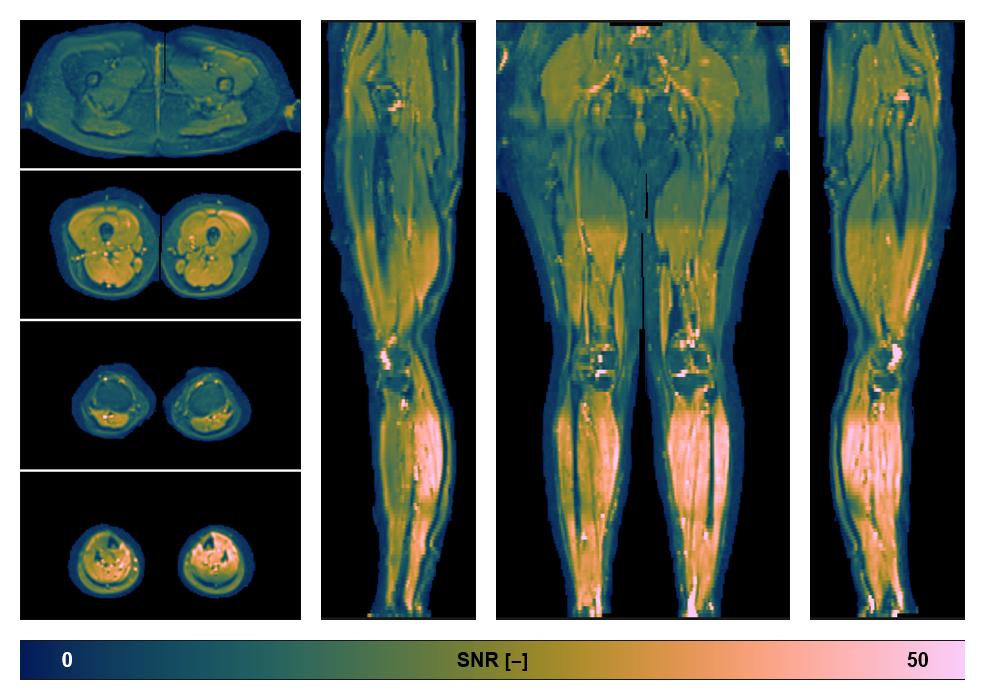

Diffusion tensor imaging

Diffusion weighted imaging with IVIM and DTI fitting to obtain muscle microstructure and muscle architecture, for information look here».

• SNR of the unweighted image

SNR distribution of the unweighted diffusion data.